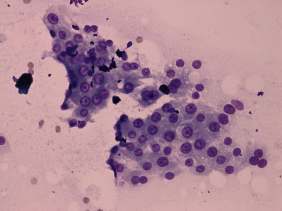

Cytology was performed from the discrete lesion in the left lobe and resulted in Hashimoto's thyroiditis.

Our final diagnosis was hypothyroidism caused by Hashimoto's thyroiditis. A benign lesion in the left lobe.